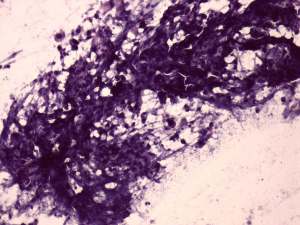

Cytology from the lymph node resulted in metastatic squamous cell carcinoma.

Histopathology disclosed a lymph node metastasis of a basaloid squamous cell carcinoma. The tumor did not spread extracapsular and was HPV-positive. Only one of the 18 removed node contained metastasis.